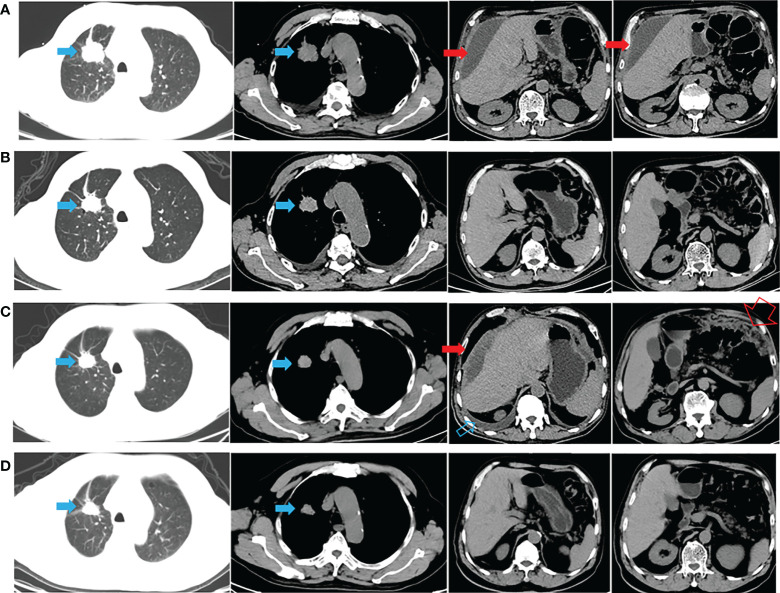

一名有大约 20 包年吸烟史的 72 岁男性主诉腹胀,于 2020 年 9 月 22 日入院。胸腹计算机断层扫描 (CT)(图 1A)和放射性核素骨扫描显示 2.8 厘米的右上肺肿块、胸水、腹水和多处骨转移(颅骨、右锁骨、多处椎骨和骨盆)。 彩色多普勒超声诊断左颈淋巴结转移。 CT引导活检示肿块为肺腺癌,诊断为右上肺腺癌多发转移(cT1bN3M1c,IVB期)。 2020 年 10 月 8 日,通过对一组 8 个癌症相关基因的下一代测序(NGS)分析了活检组织。在 EGFR 外显子 21(L858R)中检测到突变(丰度:14.5 %) 和 PIK3CA 外显子 8 (E474D)(丰度:36.6%),如图 2A 所示。 患者接受了第三代 TKI almonertinib(110 mg/d)和双膦酸盐(唑来膦酸,4 mg,q4w)的一线治疗。 最初实现了疾病稳定,但患者最终经历了疾病进展(出现胸水和腹水),无进展生存 (PFS) 时间为 12 个月(图 1B、C)。 疾病进展后,患者入住当地医院并接受顺铂(75 mg/m2,d1)和培美曲塞(500 mg/m2,d1)2个周期的化疗。 然而,胸水和腹水没有得到控制。 随后,患者入院,腹水沉渣诊断为转移性肺腺癌。 对腹水沉积物和 EGFR 外显子 21(L858R)(丰度:1.7%)、EGFR 外显子 18(L718Q)(丰度:0.8%)和 TP53 的突变进行重复检查 (V157F)(丰度:1.6%)被发现(图 2B)。

与多学科团队 (MDT) 讨论了患者的病例。 重要的是,患者已充分了解拟议治疗的益处和风险,并签署了知情同意书。 研究表明,与较高剂量的西妥昔单抗 (500 mg/m2) 相比,阿法替尼联合较低剂量的西妥昔单抗 (250 mg/m2) 可能具有更高的耐受性。 因此,2021年11月16日开始阿法替尼(40 mg/d)和西妥昔单抗(250 mg/m2,q2w)联合治疗。1个月后CT显示肺部和转移灶稳定,胸水和腹水控制良好( 图 1D)。 然后,每 2-3 个月进行一次随访,最近一次随访时间为 2022 年 6 月 8 日。 轻微的胃肠道反应是观察到的唯一不良事件 (AE)。 患者仍在接受联合方案治疗,生活质量满意,PFS近7个月。 从最初的病理诊断开始,总生存期 (OS) 超过 21 个月(图 1 )。